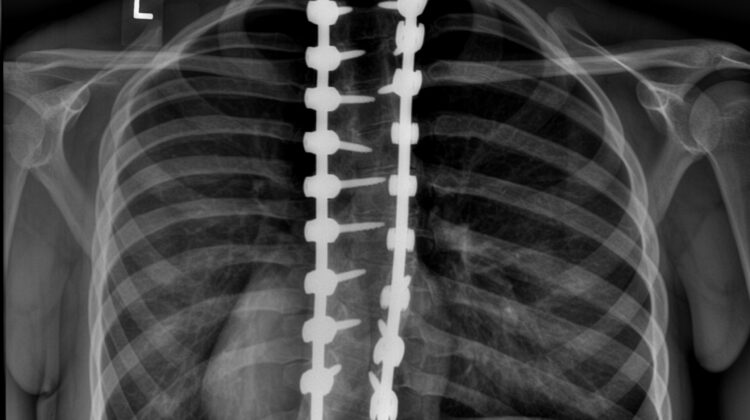

تُعد عملية تثبيت أو دمج الفقرات من أكثر الإجراءات الجراحية شيوعًا لعلاج حالات اعوجاج العمود الفقري الشديد (الجنف)، خاصة إذا تجاوزت زاوية الانحناء 45 درجة. تهدف الجراحة إلى دمج فقرتين أو أكثر معًا، مما يحدّ من تطور الانحناء ويحسن من استقامة الظهر وجودة الحياة.

عملية دمج الفقرات هي جراحة يتم فيها ربط فقرات العمود الفقري معًا بواسطة قضبان معدنية ومساميـر أو أسلاك، مع وضع مادة عظمية بين الفقرات لتلتحم تدريجيًا وتصبح قطعة واحدة.

المادة العظمية قد تكون مأخوذة من جسم المريض نفسه أو من متبرع، والهدف الأساسي هو منع حركة الفقرات المدمجة وبالتالي وقف زيادة الانحناء.

التثبيت المعدني: تركيب قضبان ومسامير لضمان استقرار الفقرات حتى تلتئم.